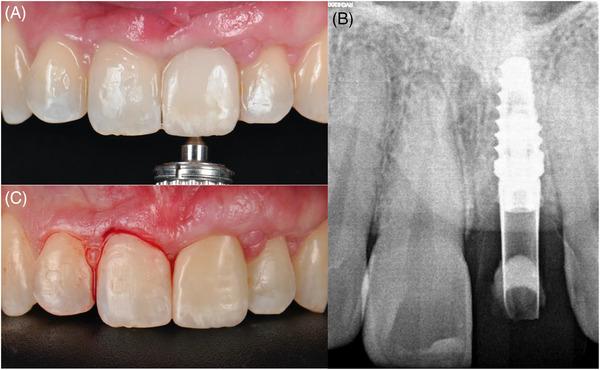

As the need for using dental implants to replace single missing teeth grows, so does the demand for greater esthetic results. However, achieving complete interproximal papillae fill in single-tooth implant restorations remains a challenge. The distally anchored connective tissue platform is a novel soft tissue augmentation technique that consists of harvesting an autogenous connective tissue graft from the palate, folding it, and positioning it at the level of the distal occlusal and buccal surfaces with the help of a distal sling suture to the adjacent distal tooth.

This case report describes how a maxillary central incisor with compromised hard and soft tissues were replaced using a comprehensive treatment plan.

The clinical outcomes showed stable mucosal margin levels and complete papillae fill. The patient expressed satisfaction with the achieved results.

The distally anchored connective tissue graft platform performed at the time of implant placement emerges as a viable and effective soft tissue augmentation technique that yields highly esthetic results.